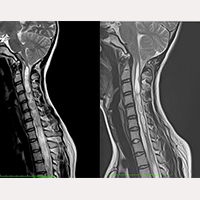

Depuis octobre 1993 jusqu’au mois de juillet 2017, plus de 1000 patients atteints du Syndrome de traction médullaire et/ou Maladie du Filum avec Arnold Chiari I, Syringomyélie et Scoliose en différentes combinaisons de diagnostic parmi elles, ont été pris en charge et opérés selon les protocoles du FILUM-SYSTEM®.